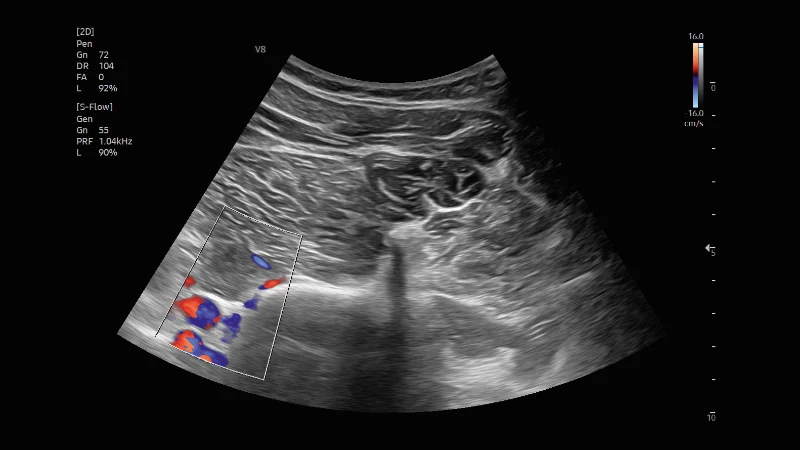

Inhalte sind wichtige allgemeine Grundlagen der Ultraschalldiagnostik und die Einführung in die sonografische Organdiagnostik in Akutsituationen (Herz, Thorax und Abdomen). Dieser Kurs bildet ebenfalls die Basis für die Zertifizierung Sonographie im Rettungsdienst.

In diesem Kurs werden systematisch Untersuchungs-techniken zur erweiterten sonografischen Organ-diagnostik (Herz, Thorax, Abdomen, Gefäße) in Akutsituationen mit den für Akutmediziner wichtigen Pathologien vermittelt.